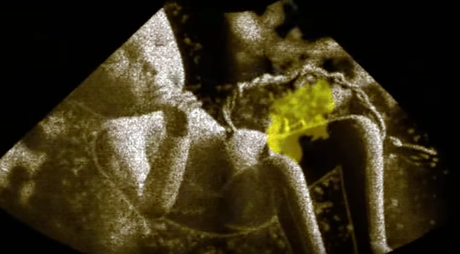

Bébé baigne dans le pipi !

Bébé baigne dans le pipi !

Ce voyage au pays de l’or liquide nous rappelle que nous avons passé les premiers mois de notre vie dans l’urine ! Car le fœtus se soulage chaque jour d'un volume d'environ deux verres d’eau. Au cours d’une vie, chacun de nous produit 38 000 litres d’urine, soit l’équivalent d’un gros camion-citerne. Pourtant, malgré ce volume impressionnant et son succès croissant, ce liquide reste un sujet tabou ! Grâce à des caméras thermiques, microscopiques et ultrarapides, une plongée captivante dans un fluide doté de multiples vertus, signée Thierry Berrod ("La fabuleuse histoire des excréments", diffusée par ARTE en 2008).